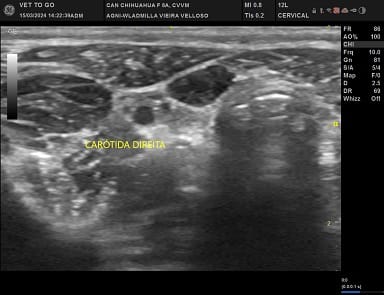

Imagens de Ultrassom Cervical Veterinário

O Ultrassom Cervical é um exame que pode ser realizado em cães e gatos e é de grande auxílio para investigar alterações na região do pescoço ventral. Através dele é possível avaliar a vascularização da região, linfonodos regionais, glândulas salivares, esôfago cervical, língua, musculatura, traquéia, laringe, tireóide e paratireóide.